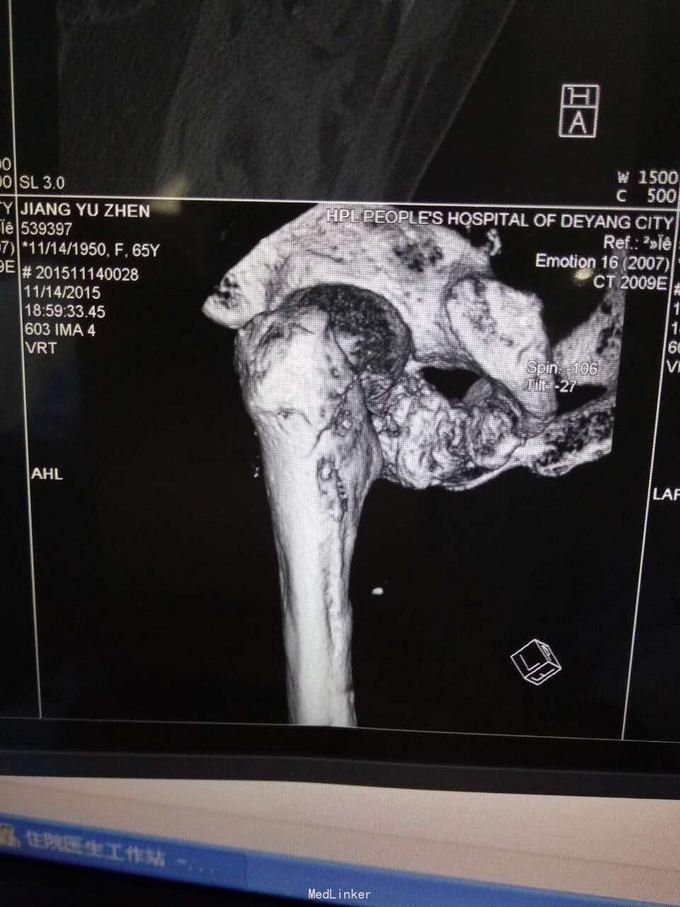

主诉:摔伤致左髋部疼痛及活动受限1小时; 病史:1小时前患者不慎摔伤,致左款疼痛,活动受限。无开放性伤口。患者半年前于华西诊断重度骨质疏松症,长期注射鲑降钙素,密固达一次。

查体,左下肢外旋畸形,髋部压痛,轴向叩击痛。 x片提示:左股骨颈、转子间骨折,左股骨耻骨上支,耻骨联合、下肢粉碎性骨折。

诊断:左股骨颈、转子间粉碎性骨折,左耻骨上支、耻骨联合、下支粉碎性骨折,重度骨质疏松症, 处理:患肢制动,牵引,注射鲑降钙素,科室讨论意见为行髋关节置换术,与换方沟通后,换方表示拒绝手术治疗,主动出院。